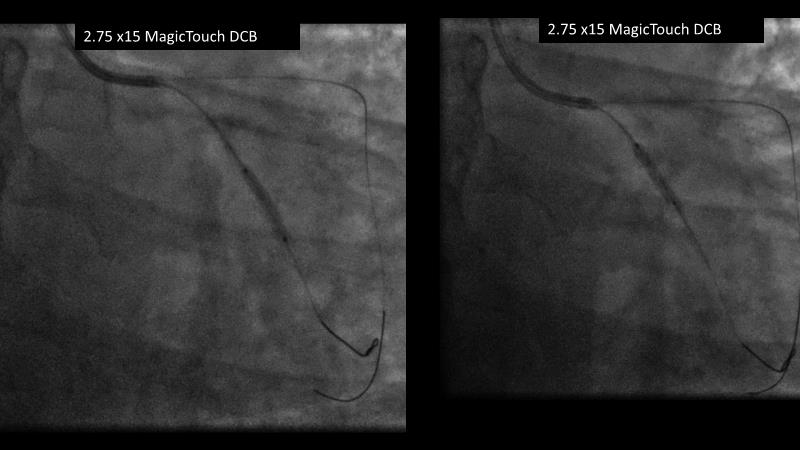

Sirolimus coated balloon: expanding the scope of coronary artery disease treatment

Consult this session to understand the technology and scientific evidence of the novel sirolimus drug-coated balloon, to learn its utility for PCI in a variety of lesion and patient subsets and to understand the evidence and outcomes in real-world patients.

- To understand the technology and scientific evidence of the novel sirolimus drug-coated balloon (SDCB)

- To learn the utility of the DCB for PCI in a variety of lesion and patient subsets